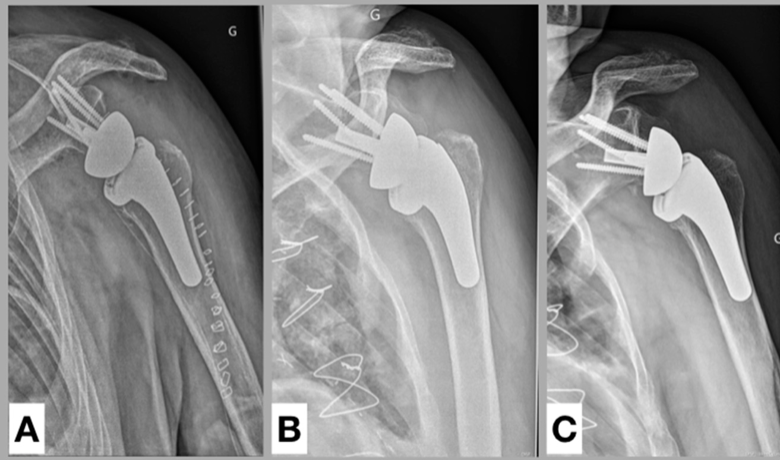

Attempts to obtain secure press-fit fixation of a short stemmed component in the humeral canal can increase the risk of periposthetic fractures as seen in Surgical fixation of periprosthetic humeral shaft fracture about a short-stem anatomic total shoulder arthroplasty with a proximal humeral locking plate: surgical technique and report of 3 cases

All of the above relates to the challenges in alignment in the AP plane. However, there are problems with controlling the position of the stem in the axillary plane as well. In the case below, one can see that posterior displacement of the stem in the humeral canal as well as posterior angulation of the implant have combined to yield posterior decentering of the head in the glenoid.